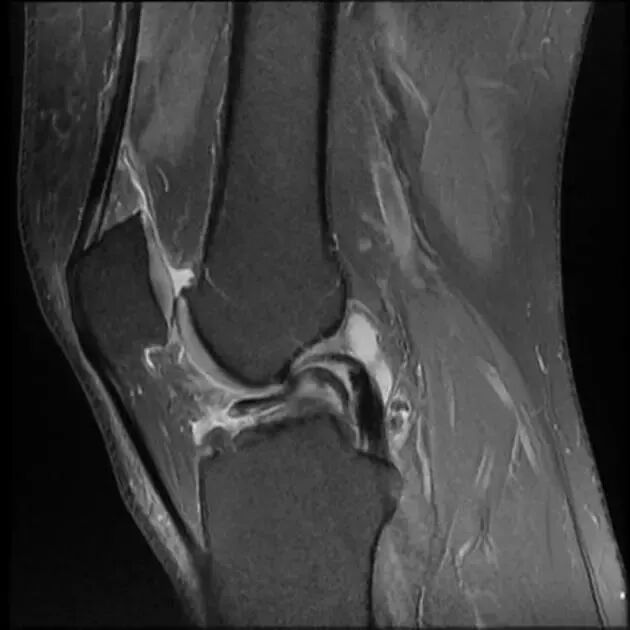

众所周知,每个膝关节后交叉韧带只有一条,下图为解剖示意图。

图1 膝关节后交叉韧带模拟图和膝关节矢状位 MRI T2WI 图像,红色箭头所指为正常后交叉韧带